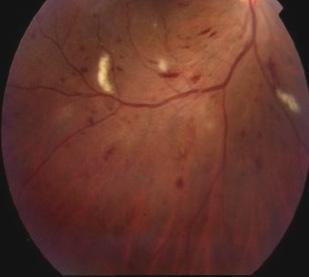

The findings in DRS may range from only a few scattered microaneurysms and dot blot hemorrhages (mild nonproliferative retinopathy) to extensive retinal hemorrhages, venous beading, cotton-wool spots and IRMA (intraretinal microvascular abnormalities), and severe nonproliferative retinopathy. Hard exudates may be seen in any stage and are often indicative of macula edema. Retinal neovascular is the hallmark of proliferative retinopahy and may or may not be associated with pre-retinal or vitreous hemorrhage.

MICROANEURYSMS (ARROWS) VENOUS BEADING DOT BLOT HEMORRHAGES

RETINAL HEMORRHAGE